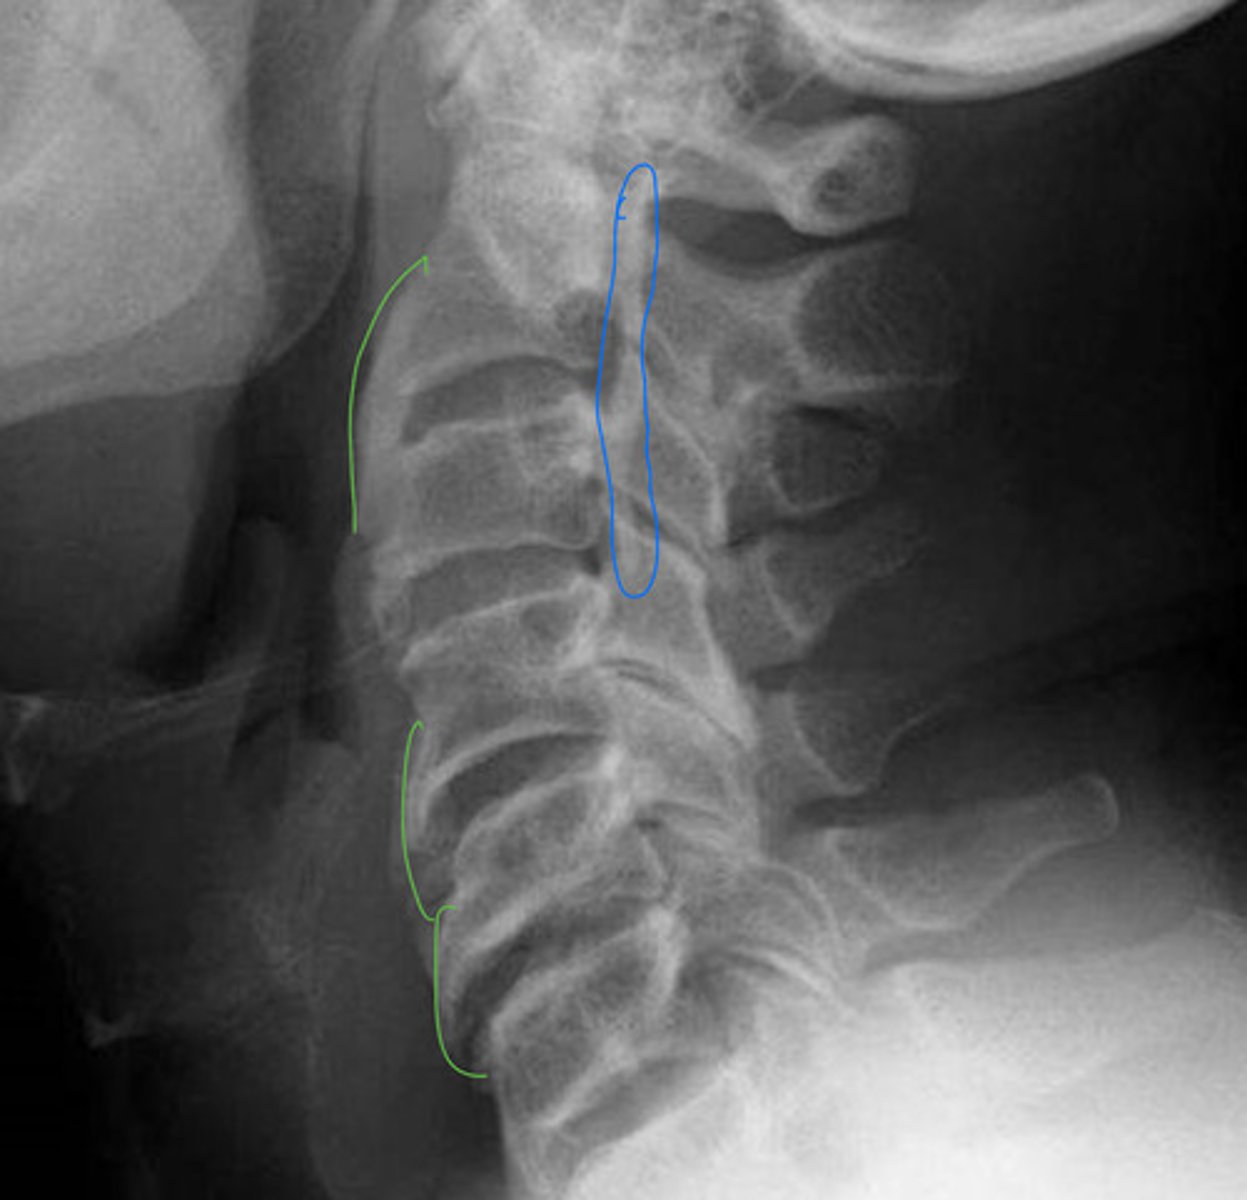

DISH/AH

What is this image showing?

Ossification of the PLL

Laminectomy

What is the pink?

Ossification of PLL

What is the blue?

AH

OPLL

What is the green?

What will cause the cord herniation

OALL (if OALL is present, always check PLL)